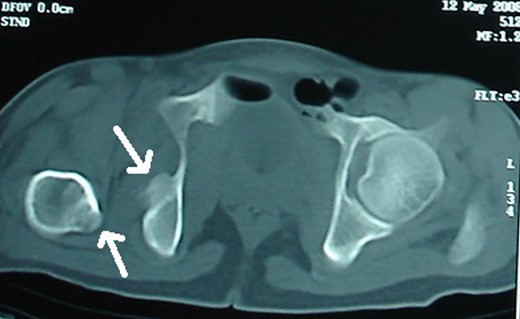

Blood parameters were within normal limits. X-ray of the pelvis revealed a right posterior hip dislocation with Pipkins's type II fracture (Rt) and ipsilateral distal medial condylar fracture with a fracture shaft of femur (Lt) (Figs 1 and 2). A CT scan confirmed the infrafoveal right-sided Pipkin's-II fracture of the femoral head (Fig. 3). A nerve conduction velocity study of lower limb suggested neuropraxia of sciatic nerve. Following attempt of closed reduction, CT scan and X-rays revealed incongruous reduction.

Initial CT scan: Pipkin's fracture (white arrow) with posterior dislocation right hip.